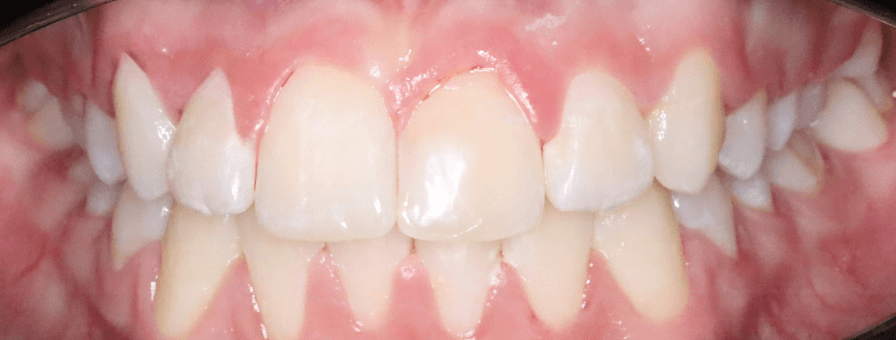

Tratament Ortodontic Fix pentru Înghesuiri Severe

Am tratat cazul cu aparat fix bimaxilar, după o evaluare completă a complexității și a necesarului de spațiu. Cazul a fost finalizat în aproximativ 1 an.